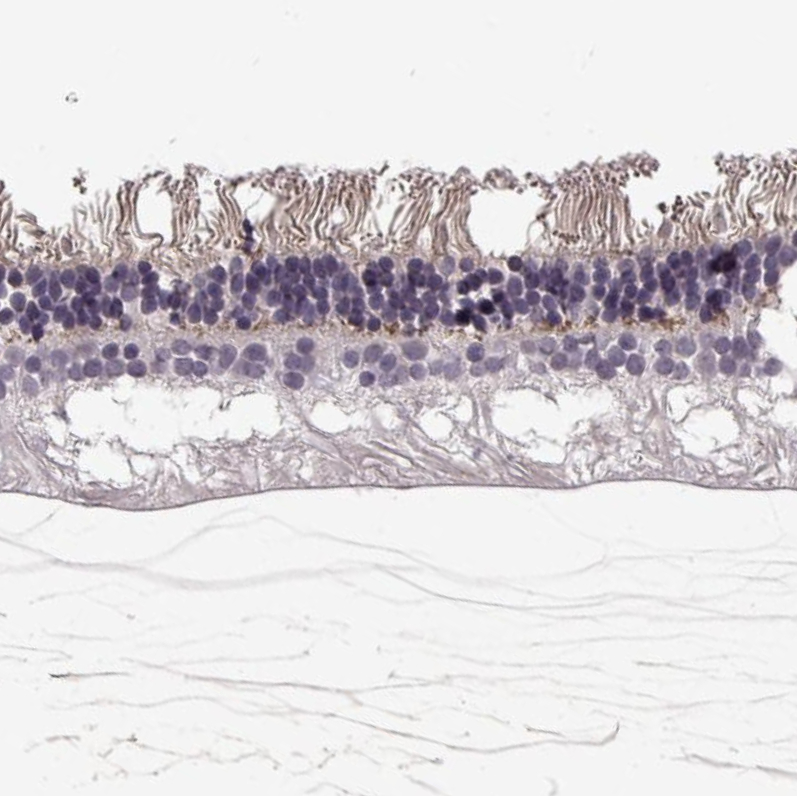

Immunohistochemical staining of human retina shows weak to moderate membranous positivity in the outer plexiform layer.